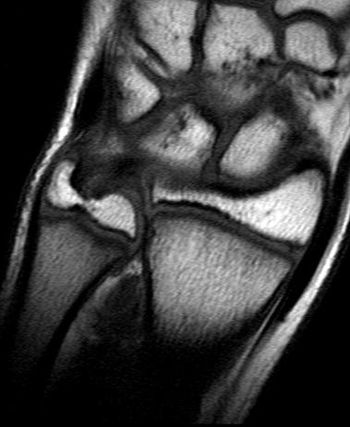

MRI has been adopted as a definitive measure for fair play by the International Federation of Association Football, the governing body for international soccer competition. FIFA will launch a program of random MRI wrist screening to verify the age of players competing in the Under-17 World Cup hosted by Nigeria Oct. 24 through Nov. 15.

MRI has been adopted by the International Federation of Association Football as a definitive measure to ensure fair play.